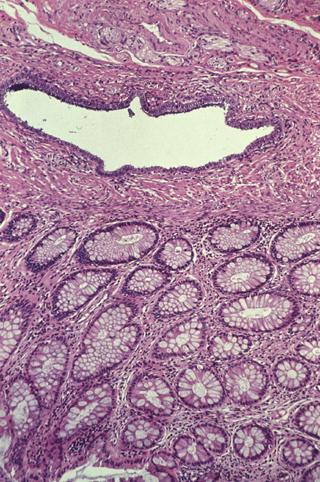

Endometriosis causado por canal intestinal, que fue operado por motivo constricción de Colon Signoides.

Lesión que asemeja tumoración/Mucosa aberrante

colon/sigmoides

Micro